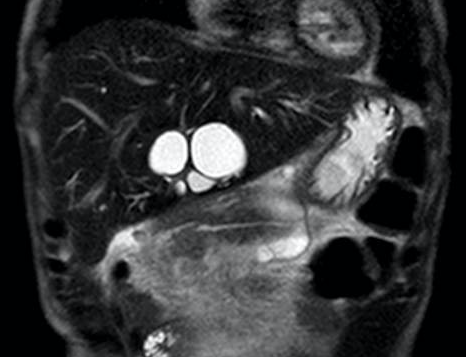

Case 2: a 52 y old man, with a MVT for diffuse portomesenteric thrombosis, Budd-Chiari syndrome and a thrombosed portocaval shunt. He showed cholestasis since 2 weeks of the procedure, initially related to drug toxicity, but progressively deteriorated, and biliary sludge was shown after several weeks, an ERCP failed, a PTC was done and a bile cast shown. Repeated ERCPs were done for cholangitis and stent exchange, and he developed intrahepatic massive biliary dilation (see figures 1 and 2). Over time, antibiotic resistant bacteria were isolated. A left liver lobe resection and bilioenteric anastomosis were done with the aim to stop these complications, but a severe sepsis developed and the patient subsequently died, 2 1/2 years after the MVT.